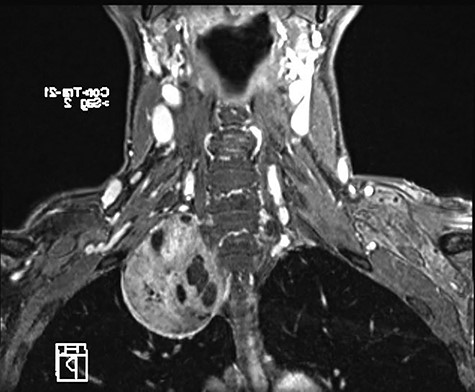

A 58-year-old female smoker with a history of cosmetic surgery complained of a large supraclavicular cervical mass associated with some neurological disorders (including anisocoria and ptosis of the right eyelid) since 2014. An ultrasound of the neck with cytological examination raised the suspicion of ‘Schwannoma’ with liquid content. Computed tomography (CT) of the neck and chest confirmed the presence of a 6.6 × 6 cm paracervical and paramediastinal right mass that dislocated the trachea and esophagus. The injury was also confirmed by nuclear magnetic resonance imaging (MRI) of the neck and chest (Figs 1, 2).

MRI showing paravertebral neurinoma with liquid content (C7-D3) with right intrathoracic involvement compressing the mediastinal structures without signs of vascular infiltration.

MRI of paracervical neurinoma in the coronal projection affecting the right paravertebral structures.